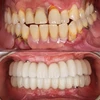

Zirkonyum uygulamalar

Porselen uygulamaları

Laminate veneer